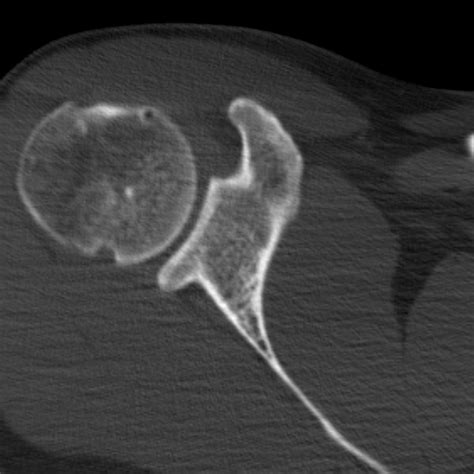

• CT Scan (Computed Tomography): This can offer a more detailed view of the bone structure and is often used to assess the extent of the fracture.

A Hill Sachs Fracture is a specific type of injury that occurs in the shoulder joint. It involves a compression fracture of the humeral head, which is the upper part of the arm bone that fits into the shoulder socket. This fracture typically results from a dislocation of the shoulder, where the humeral head is forced out of its socket and then impacts the glenoid rim, causing a depression or fracture on the humeral head.

• hill sachs fracture ct